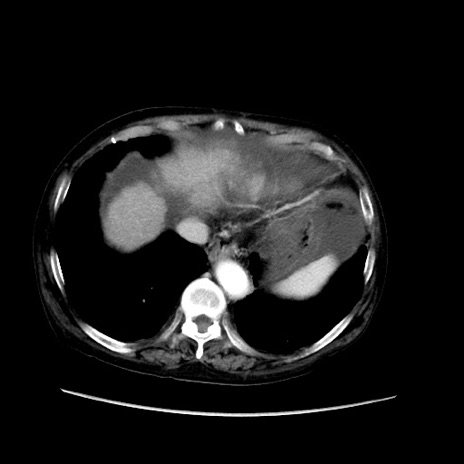

症例31(横断像)

【症例】80歳代 女性

【主訴】腹部膨満感

【現病歴】他院にて肝硬変にてフォロー中。1週間前から便秘、腹部膨満感、臍部腫瘤あり受診となる。

【既往歴】肝硬変

【身体所見】腹部膨隆あり、皮膚変化なし、疼痛なし。

【データ】WBC 4600、CRP 0.25